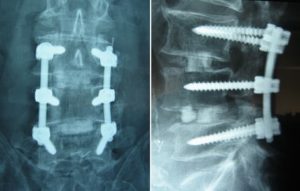

Now that we have looked at the numbers, let’s look at what a spinal surgery potentially can do for you, and what it can’t. The objective of decompression surgery is to reduce pressure on the nerves exiting from the spine. For a decompression and fusion surgery, in addition to reducing nerve pressure, one or more spinal joints are immobilized, typically using a plate and screws.

At best, this may reduce the patient’s symptoms. Surgery does not address what caused the condition in the first place. In most cases disc herniation/degeneration, stenosis, spondylolisthesis, and degenerative arthritis are caused by abnormal spinal mechanics. This includes altered posture, muscle imbalances, and impaired strength and stability.